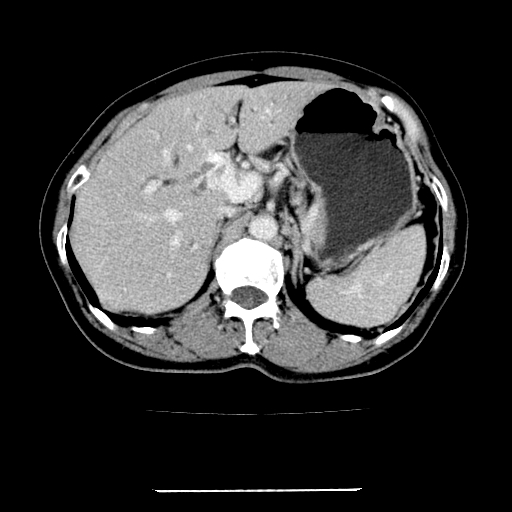

标题: CT22301:女,67岁,上腹部疼痛一周伴皮肤黄染,无发热。 [打印本页]

女,67岁,上腹部疼痛一周伴皮肤黄染,无发热。

左叶肝内胆管结石,并远端肝内胆管扩张。

考虑:肝内胆管结石继发肝内胆管扩张,右肾旋转不良。

肝内外胆管结石并肝内胆管扩张。

肝内外胆管结石并肝内胆管扩张

肝内外胆管扩张,左叶胆管内结石

建议薄层观察,除外肝门部胆管细胞癌

考虑肝胆管癌;胰头占位?【形态失常,体积增大】

1、肝门高密度影下层面和胰头层面可见轻度胆管扩张,而静脉和延迟期均未见扫描完胰头,不能完全排除胰头占位。2、肝门部高密度影,考虑钙化或结石。

考虑肝门胆管癌伴门脉左支受侵包埋,建议mrcp进一步检查。

肝内胆管结石并胆管扩张